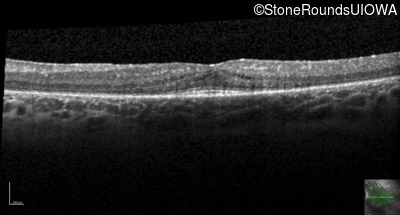

| Age at visit: 27 years |